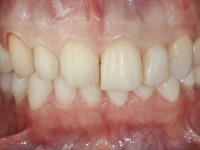

Paciente do sexo masculino, com 36 anos, não fumador. Fez tratamento ortodôntico e reabilitou esteticamente o sector anterior com restaurações em resina composta. As restaurações apresentavam um aumento vertical médio de 2 mm em relação o bordo incisal. Apresentavam-se esteticamente satisfatórias, mas com algumas fraturas incisais. O dente 1.5 apresentava um processo apical e o dente 2.6 apresentava tratamento endodôntico e uma lesão endo-periodontal. No maxilar inferior no local do dente 3.5 apresentava um implante com uma coroa aparafusada e o dente 8.5 ainda estava presente em boca com agenesia do dente 4.5. O paciente apresentava uma ligeira perda da dimensão vertical da oclusão provavelmente associada a um visível desgaste das superfícies oclusais. O periodonto era espesso e apresentava uma excelente higiene oral.